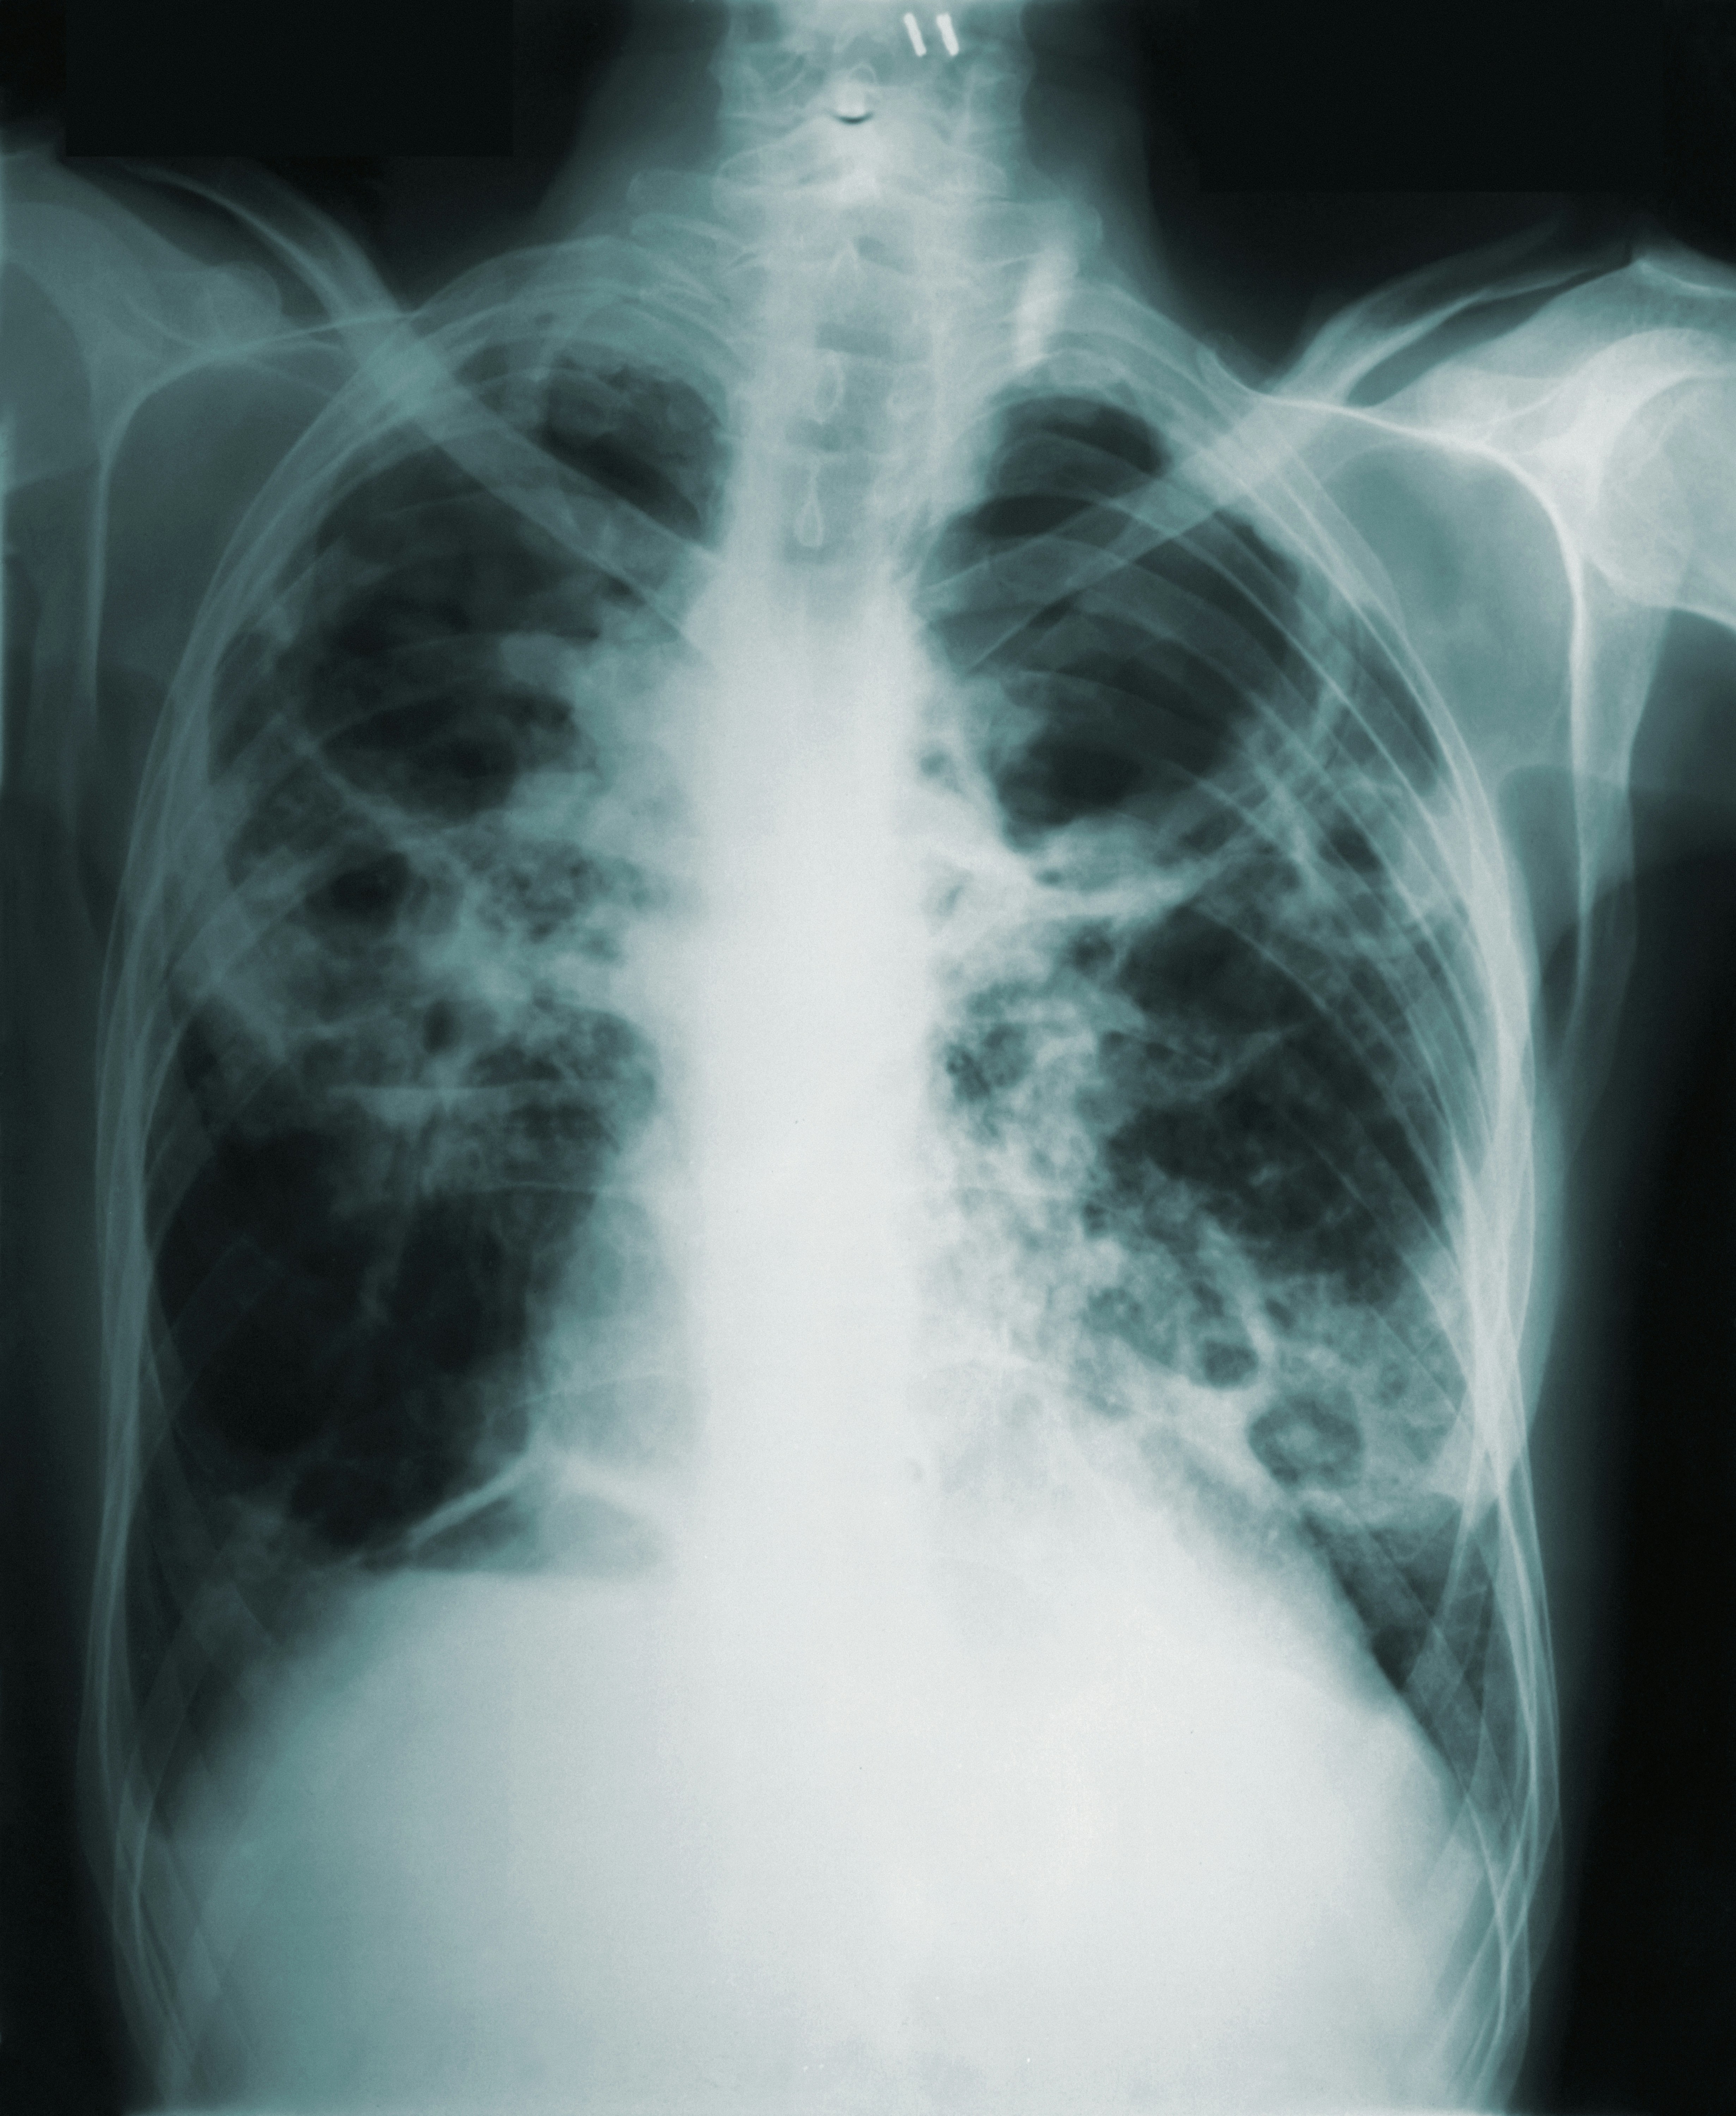

3. 폐 기능 향상 (BDNF 수치 상승 및 폐포 정화)

기관지가 이완되어 호흡이 한결 가벼워지고 폐의 산소 흡수 능력이 증가합니다. 계단을 오를 때 숨이 덜 차는 것을 몸소 체감하게 되는 시기입니다.

금연 1개월에서 9개월 사이에는 폐 속의 섬모가 다시 자라나 폐 청소 기능을 수행하며 기침과 코막힘이 사라집니다. 만성적인 피로감이 줄어들고 전신의 염증 수치가 급격히 낮아집니다. 특히 **1년**에 도달하면 심장질환에 걸릴 위험이 흡연자의 절반 수준으로 뚝 떨어지는 **'신체 리셋'** 현상이 일어납니다.

| 3개월~9개월 | 폐 섬모 재생 및 폐활량 증가 | 면역력 및 폐기능 정상화 |